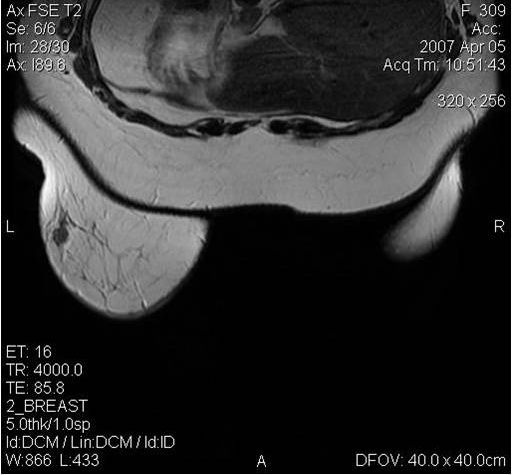

Магнитно-резонансная томография

Поскольку традиционный маммографический скрининг у женщин до 40 лет малоэффективен, для скрининга может понадобиться альтернативная методика — МРТ. Современная контрастная магнитно-резонансная томография — высокочувствительный метод диагностики заболеваний молочной железы.

МРТ-диагностика рака молочной железы

У женщин с мутациями BRCA1 или BRCA2 при проведении МРТ возможно диагностировать рак молочной железы на самых ранних стадиях.